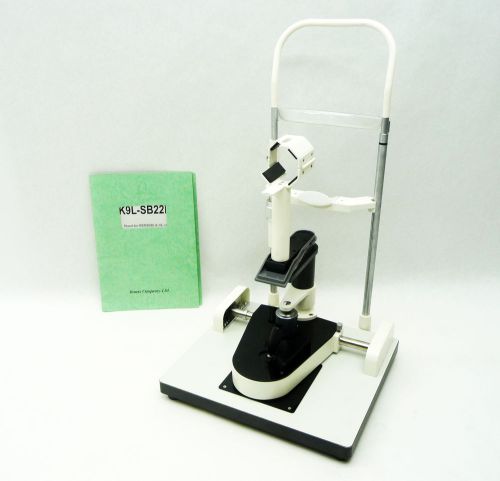

Brand | DEC |

| Model | DC-IP-6PLUS |

Kowa K9L-SB22K Ophthalmic Fundus Camera Slit Lamp Chin Lift Stand Genesis SL14